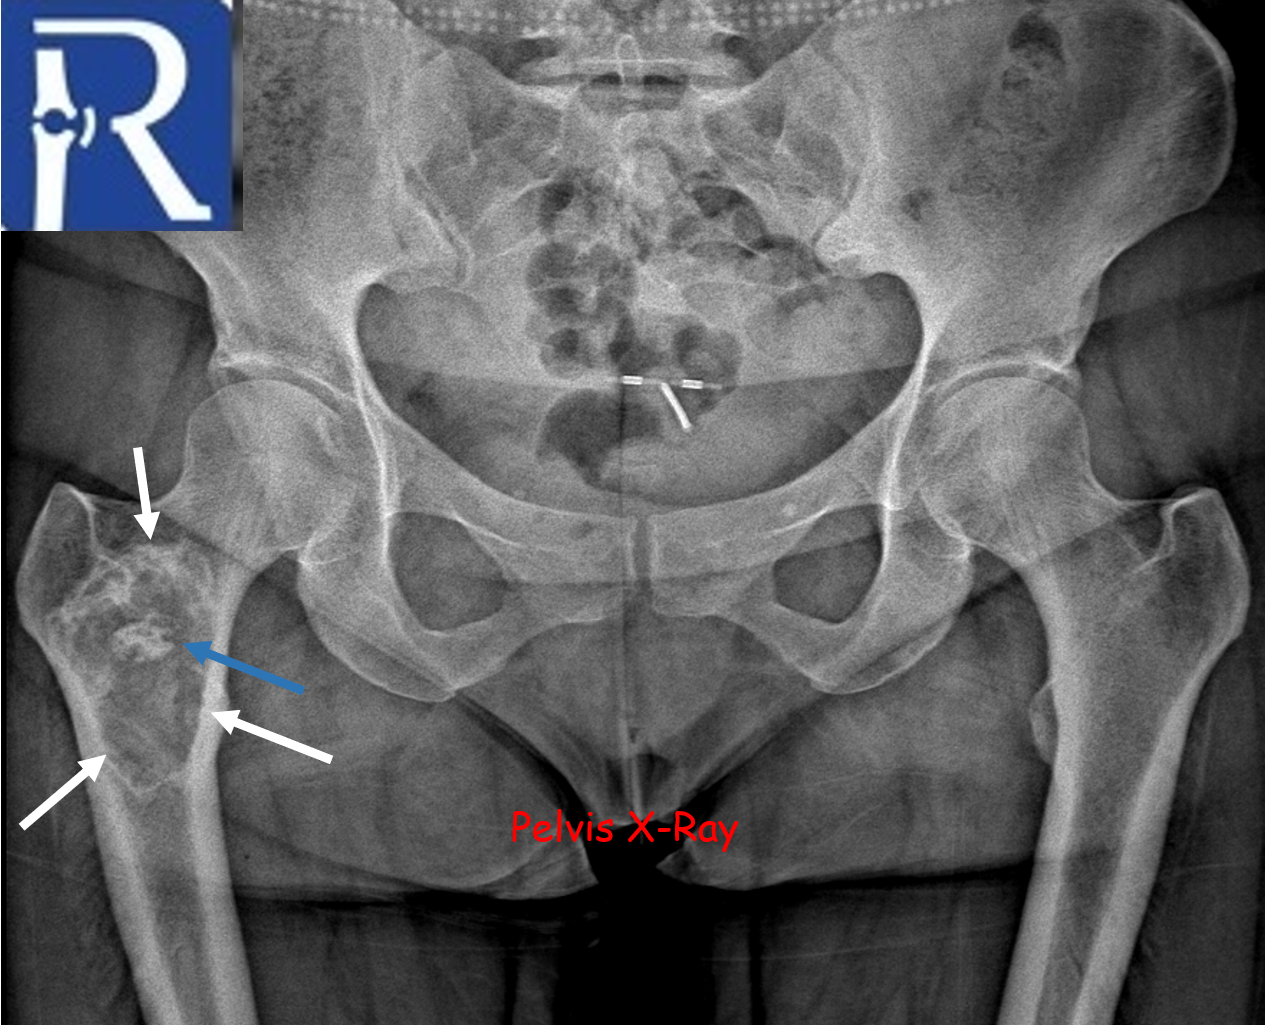

A geographic lytic lesion of Type I A pattern (white arrows) is observed on the right femur intertrochanteric-subtrochanteric area on the pelvic radiograph. The lesion is well-circumscribed and has a narrow transition zone. The internal content contains calcification (indicated by the blue arrow). Periosteal reaction is not visualised. The lesion demonstrates sclerotic areas corresponding to internal calcified foci. The lesion is compatible with liposclerosing myxofibrous tumors. In CT, the lesion matrix structures are more clearly visible, and the cortex appears intact. Calcification areas in the internal structure are more clearly observed. In MRI, the lesion appears as a low signal on the T1-weighted (T1W) sequence and as a high signal on the short tau inversion recovery (STIR) sequence, representing the myxoid content. Additionally, the calcification areas within the lesion exhibit low signals in both sequences.